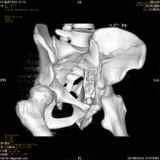

Уважаемые коллеги! Хотелось бы услышать совет по тактике лечения представлленого больного.

Поступил после лечения в одном изотделений области. Травма 2,5 месяца назад.

После выведения

из шока был произведен остеосинтез перелома бедра, предплечья, до перевода к нам проводилось

вытяжение по оси шейки бедра за стержень, введенный в большой вертел. На сегодня деформация

ригидна, клинически мобильности не определяется.